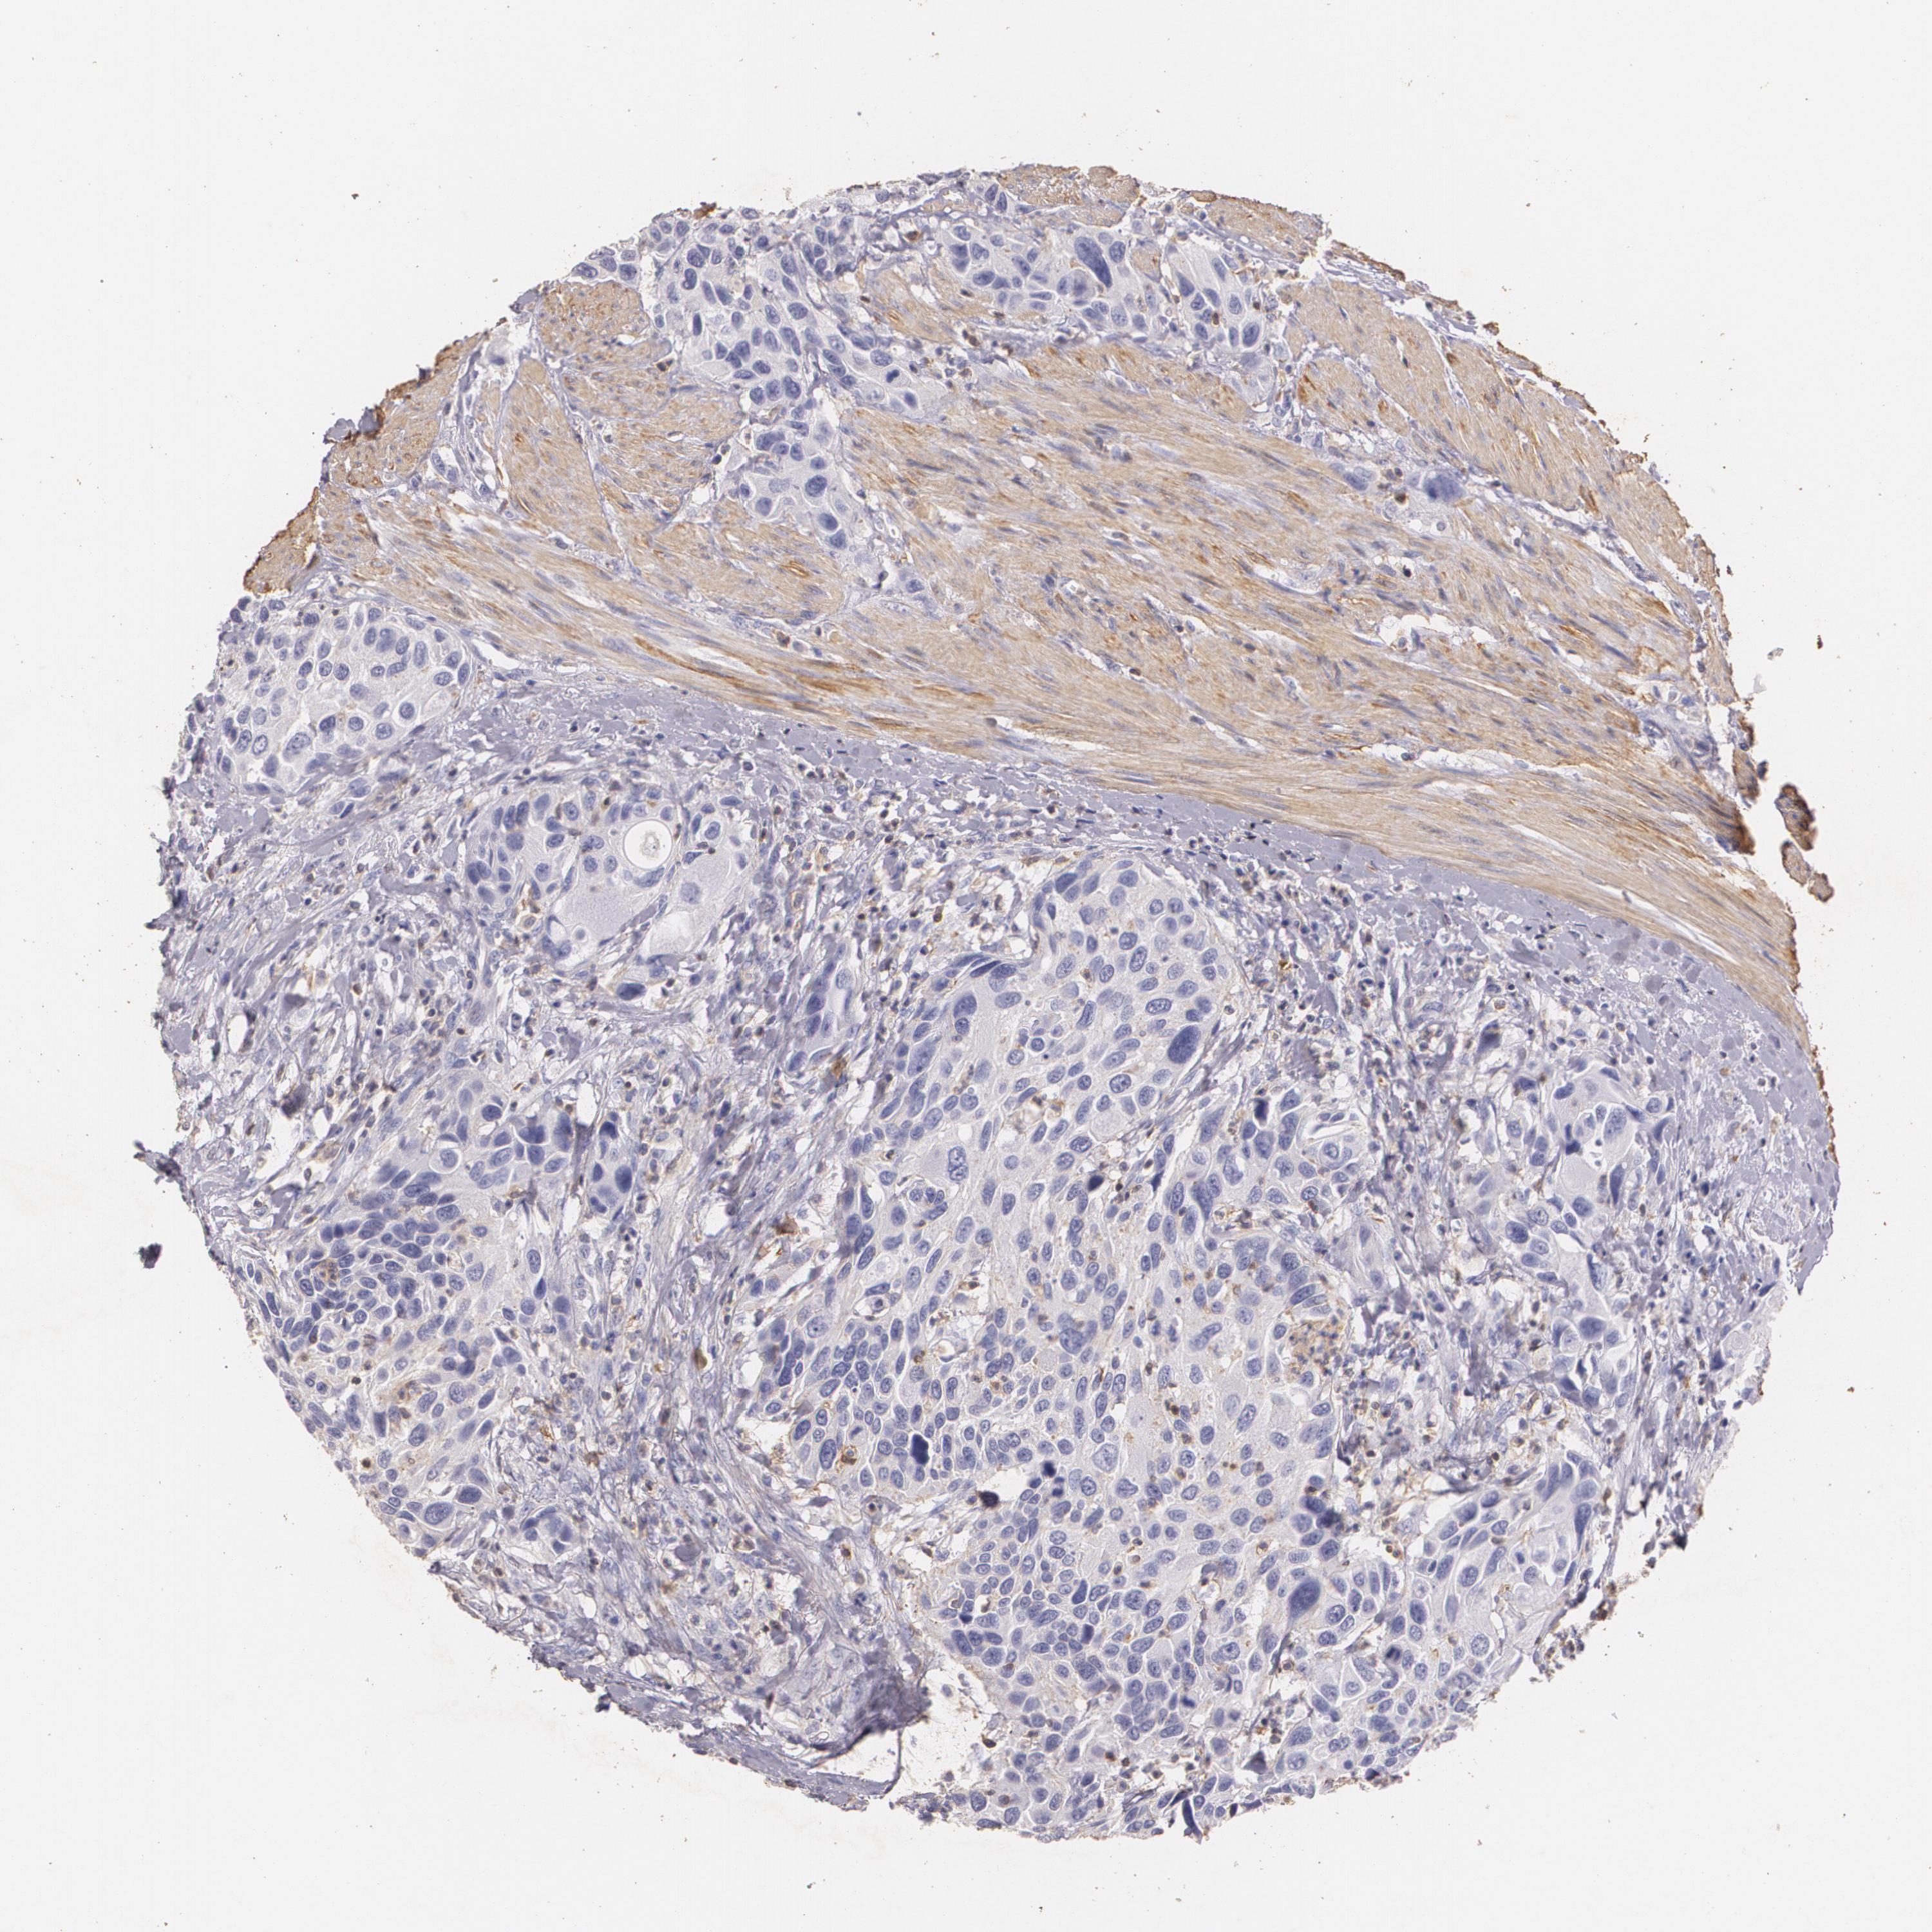

UROTHELIAL CANCER - Protein expressioni

A mouse-over function shows sample information and annotation data. Click on an image to view it in a full screen mode. Samples can be filtered based on level of antibody staining by selecting one or several of the following categories: high, medium, low and not detected. The assay and annotation is described here.

Note that samples used for immunohistochemistry by the Human Protein Atlas do not correspond to samples in the TCGA dataset.

Antibody stainingi

Antibody staining in the annotated cell types in the current human tissue is reported as not detected, low, medium, or high, based on conventional immunohistochemistry profiling in selected tissues. This score is based on the combination of the staining intensity and fraction of stained cells.

Each image is clickable and will lead to virtual microscopy that enables deeper exploration of all samples and also displays staining intensity scores, fraction scores and subcellular localization as well as patient and tissue information for each sample.

Antibody CAB002441

Antibody CAB031481

Staining

High

Medium

Low

Not detected

Intensity

Strong

Moderate

Weak

Negative

Quantity

>75%

75%-25%

<25%

None

Location

Nuclear

Cytoplasmic/membranous

Cytoplasmic/membranous,nuclear

Urothelial carcinoma, High grade

Urothelial carcinoma, Low grade

Adenocarcinoma, NOS